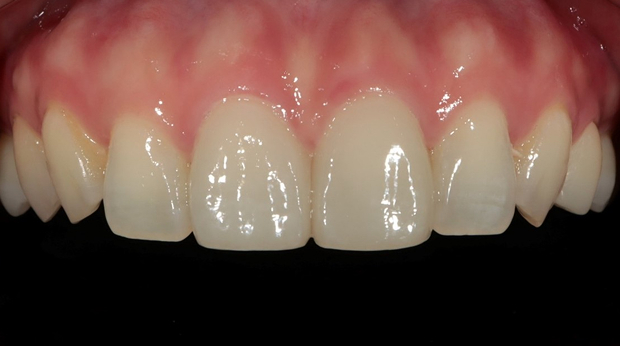

라미네이트